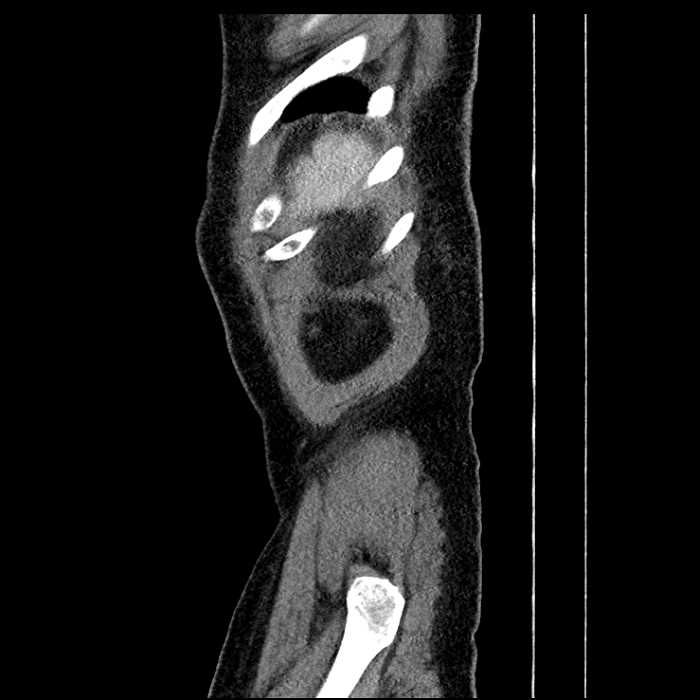

Age: 63

Sex: Male

Indication: Abdominal pain

• Large fluid density structure in hepatic segments 7 and 8 measuring 10 x 7 x 7 cm with internal septation and circumferential ill-defined low density compatible with edema

• Peripherally enhancing subcapsular collections along the anterior margin of the left hepatic lobe measuring 3 x 1 cm and 2 x 1 cm

• Clearly marginated fluid density structure in segment 7 and several other scattered tiny hypodensities, which likely represent cysts

• Hepatic abscess

Acute sigmoid diverticulitis complicated by a small contained perforation and a large abscess in the right hepatic lobe. Additional small subcapsular abscesses along the anterior margin of the left hepatic lobe.

• The classic CT imaging appearance is a double target sign with internal low density surrounded by an internal enhancing rim (capsule) and a low density external rim (edema)

• Abscesses may be unilocular or multilocular

• Gas is present in a minority of cases

Hepatic abscess showing the double target sign with low density internally surrounded by a thin inner enhancing rim (red arrow) and ill-defined outer low density rim (yellow arrow). Blue arrow indicates an internal septation. Red arrows: additional smaller subcapsular abscesses. Red arrow: focal contained perforation associated with diverticulitis.